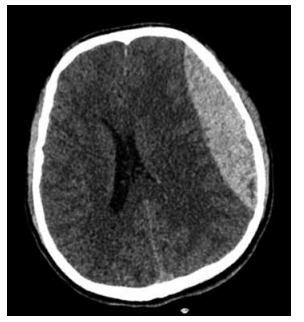

Adolescente de 13 anos de idade é trazido ao pronto-socorro por episódio de queda da bicicleta com traumatismo da região lateral da cabeça. Inicialmente, ele se apresentava alerta, porém, após 25 minutos do acidente, evoluiu com diminuição do nível de consciência. Tomografia de crânio sem contraste realizada na urgência demonstra o achado a seguir.

A estrutura vascular mais provavelmente acometida neste quadro é: